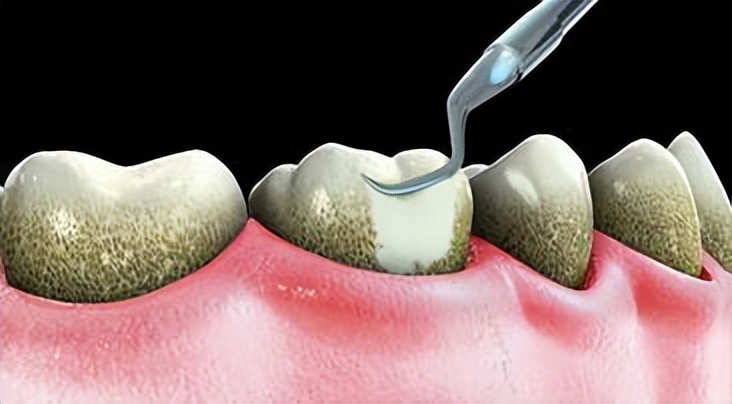

定期洗牙

每隔半年到一年请牙医洗牙,尤其是钙化后的牙结石或囊袋深部的食物残渣、牙齿斑或者牙结石,只有靠牙医才能清除干净。

如果已经发现形成牙结石,必须尽快去牙科洗牙,因为牙结石会造成牙周炎和其他口腔炎症。